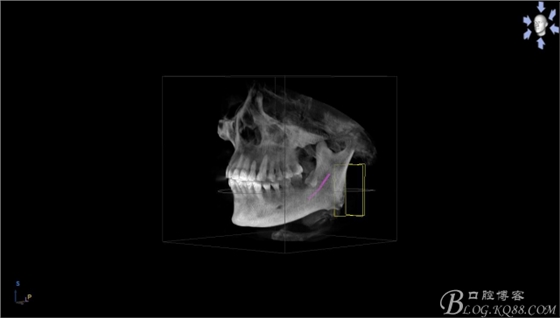

一、術(shù)前CBCT影像資料